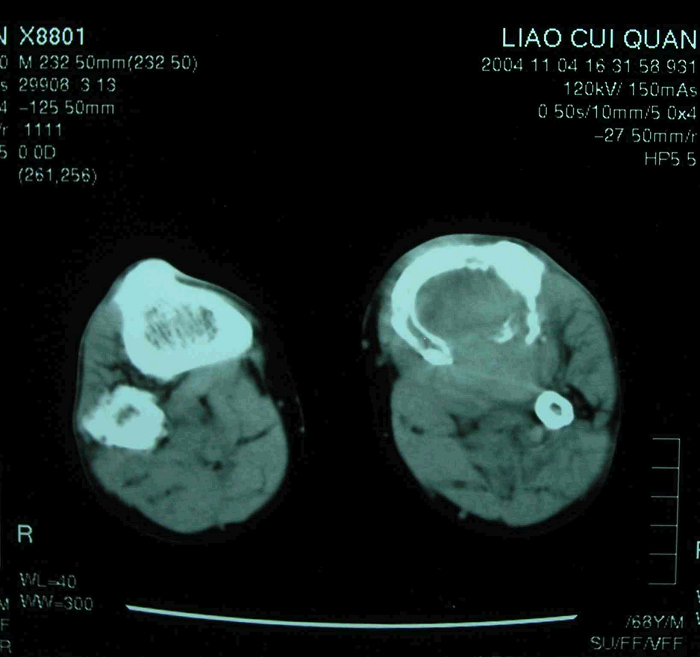

5、病例5:男 65岁 左胫骨上段毛细血管扩张性骨肉瘤,因活检术后持续性出血,行大腿中段截肢术

图 28 术前CT横断面象